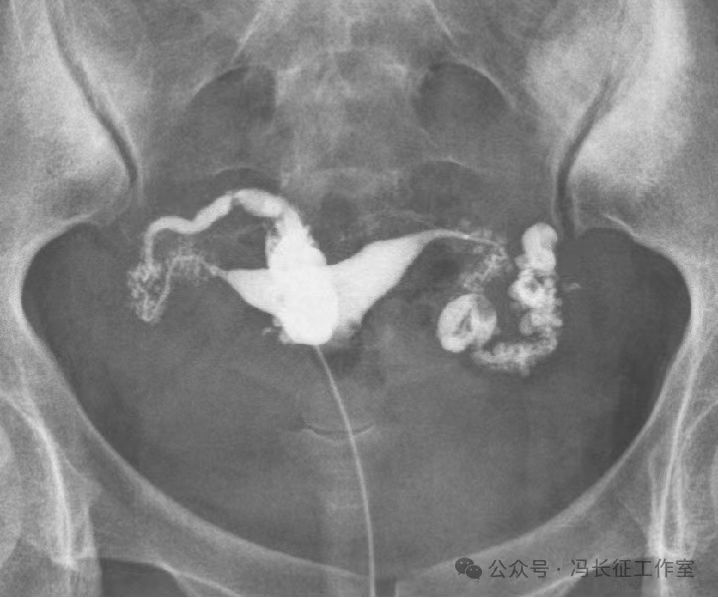

输卵管积水的子宫输卵管造影尽量包括这5个方面的描述,诊断的临床意义才最大,这样才能给好的生殖科医生有价值的建议,帮助给不孕者制定最好的助孕治疗方案。比如这例输卵管积水,峡部结节性输卵管炎(病因),交通性(积水近端是否和宫腔相通),中度(积水大小),厚壁(管壁的厚度),多囊(囊腔的多少)。

微信图片_20240220111146(3).jpg

最后诊断应该是:双侧峡部结节性输卵管炎并双侧中度、厚壁、多囊、交通性输卵管积水。